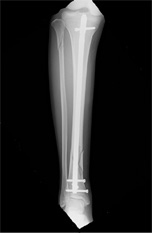

下腿骨折(すねの骨折)

バイクや自転車など交通事故で直接下腿をぶつけたりねじったりした時に生じる骨折です。

早期社会復帰のために手術が選択されることが多いものです。

• 画像:骨折観血的手術(下腿)髄内釘

骨折観血的手術(下腿)

髄内釘